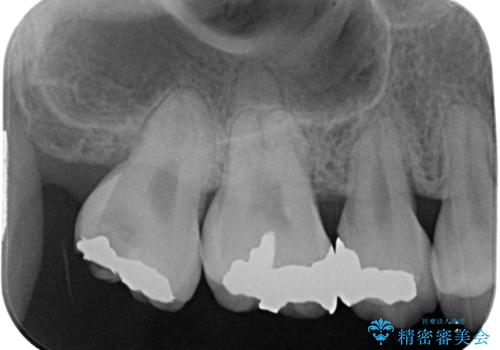

矯正治療により処置が可能な位置に歯が移動したため、オールセラミッククラウンにて補綴治療を行うこととしました。

歯列が移動したとはいえ、左右ともに後方傾斜しており、むし歯の除去、形成(形を整える)、型取りの全てが非常に困難な処置となりました。

セラミッククラウンの適合はレントゲン写真からも分かる通り、境界がぴったりと合った、高適合のものとなりました。